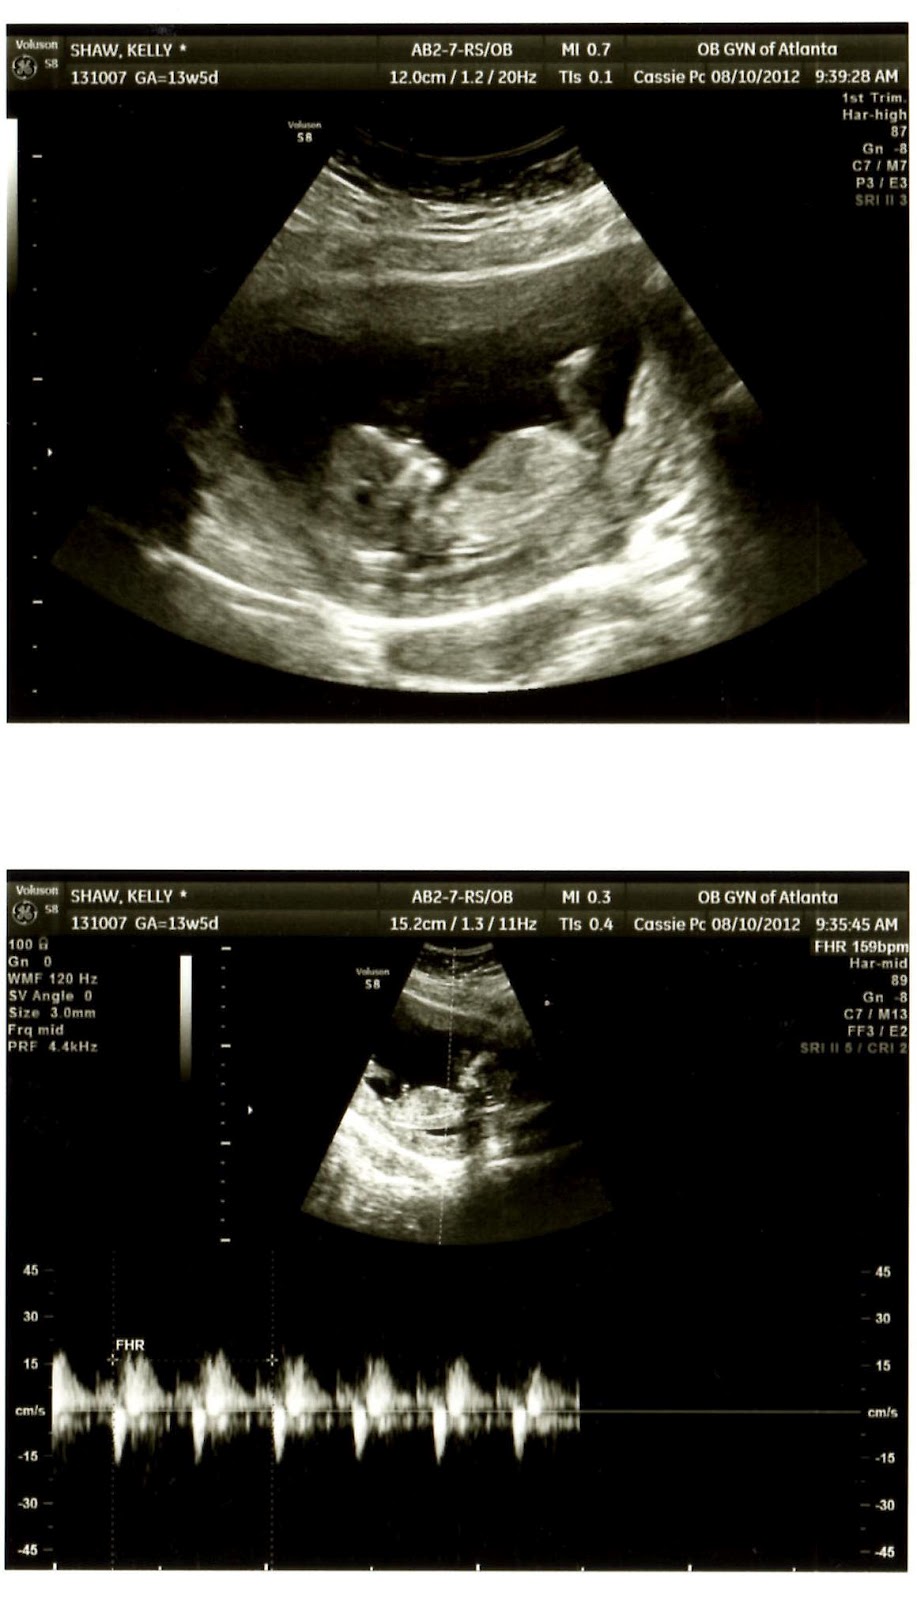

- All of these things (especially the diet/cravings, food aversions, exhaustion and chest changes!) led me to believe that I was definitely pregnant – but was of course going to leave it to the experts who confirmed my suspicions! Can't WAIT for my next ultrasound! Speaking of Next Steps...

Tomorrow: I have another ultrasound where we'll find out the sex of the baby! I'm bringing these two pictures with me, and plan to ask the doctor to not tell me, but to instead toss the picture that doesn't match the sex!